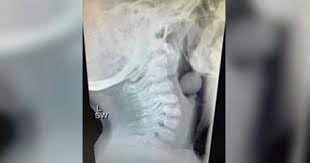

Avustralyalı bir anne olan Angela Henderson, sosyal medyada paylaştığı gönderisiyle bu duruma dikkat çekti. Gördüğünüz röntgen, 5 yaşındaki bir çocuğun yemek borusuna ait. Röntgene dikkatlice baktığınızda çocuğun yemek borusuna yuvarlak bir cismin takıldığını görüyorsunuz. Çocuk, boğazına takılan üzüm tanesinin yemek borusunu tamamen tıkamadığı için şanslıydı.

Eğer üzüm tanesi biraz daha büyük olsaydı çocuk bugün yaşamıyor olabilirdi.

Ebeveynler bu konuda dikkatli olsa da tekrardan hatırlatalım. 5 yaş altındaki çocuklara yemek verecekken, yemeği en ince tanesine kadar parçalamayı unutmayın.

Çocuklar beş yaşında da olsa yemek borusunu büyük yiyecekler tıkayabiliyor.

Öte yandan çocukların yemek yerken dik durması gerekiyor. Hareket halindeyken kesinlikle bir şeyler yememeliler.Bir konuda daha ebeveynleri uyarmak gerekiyor. Fıstık ezmesi gibi boğaza kolayca yapışabilen ve sakız gibi kolayca yutulabilen şeyleri çocuklarınıza kesinlikle vermeyin.Pedagog olan Henderson, çocukların sürekli bir telaş içinde olduğunu söylüyor ve ebeveynlerine çocuklarına yiyeceklerini çiğnemelerini hatırlatmalarını tavsiye ediyor.